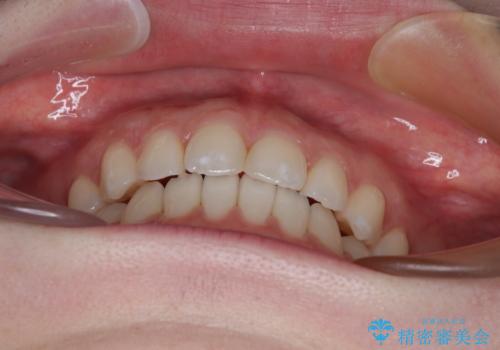

すきっ歯をインビザラインできれいな歯並びに改善

- 前歯の隙間を気にして来院された患者様です。

隙間や叢生の程度はそれほど著しいものではなかったので、インビザラインでもワイヤー矯正でも対応可能でしたが、極力目立たない装置を希望されたため、インビザラインにて矯正治療を行うこととしました。